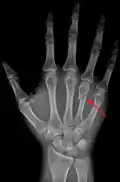

A fracture of the fourth and/or fifth metacarpal bones transverse neck secondary due to axial loading is known as a boxer's fracture.[1]

A fractured right hand fourth metacarpal (boxer's fracture).